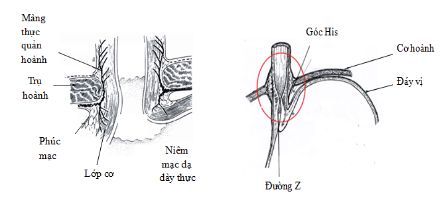

Dạ dày là phần phình to nhất của ống tiêu hóa, phía trên nối với thực quản, phía dưới nối với tá tràng. Về cấu trúc, dạ dày có bốn phần chính: tâm vị, đáy vị, thân vị và môn vị. Tâm vị là điểm nối thực quản với dạ dày, thức ăn từ thực quản đi qua tâm vị để vào dạ dày không có van đóng kín mà chỉ có nếp niêm mạc, gọi là nếp van thực quản dạ dày. Đáy vị hình vòm, nằm ở phía dưới cơ hoành, bên trên và bên trái so với tâm vị. Bên dưới đáy vị là thân và là phần chính của dạ dày. Môn vị hình chiếc phễu giúp nổi dạ dày và tá tràng. Cơ thắt môn vị (một loại cơ trơn) nằm ở phía cuối của chỗ nối giữa dạ dày với tá tràng.

Nếp van thực quản – dạ dày nằm ở chỗ nối giữa thực quản và dạ dày.

Trong quá trình nội soi tiêu hóa, khi đưa quan sát các phần của dạ dày ở tư thế máy thẳng, bác sĩ nội soi sẽ quặt ngược dây soi để khảo sát các vùng của đáy vị, tâm vị dạ dày, khi đó, sẽ quan sát được hình ảnh các nếp niêm mạc hội tụ tại chỗ nối thực quản – dạ dày, đó là nếp van thực quản – dạ dày.

Chỗ nối dạ dày-thực quản (GEJ) là khu vực giải phẫu nơi thực quản đoạn xa nối với dạ dày đoạn gần. Trong điều kiện bình thường, nó nằm ở vị trí ngang với khe hoành. Tuy nhiên, vị trí của GEJ không cố định và di chuyển vài cm trong quá trình nuốt và hít thở. Trong quá trình nuốt, cơ trơn dọc của thực quản co lại làm ngắn thực quản, dẫn đến một thoát vị sinh lý. GEJ sau đó được quay trở lại vị trí ban đầu của nó bằng các cấu trúc hỗ trợ đàn hồi, đặc biệt là bởi màng thực quản - hoành. Khi GEJ cùng với cơ vòng thực quản dưới (LES) và tâm vị dạ dày bị dịch chuyển kéo dài lên trên vào khoang lồng ngực qua cơ hoành, khi đó, tình tràng thoát vị khe hoành sẽ xuất hiện. Các nghiên cứu đã chỉ ra rằng thoát vị khe hoành làm giảm áp lực LES và chức năng cơ vòng của cơ hoành. Sự hiện diện và chiều dài trục của khối thoát vị gián đoạn cũng được chứng minh là tương quan với mức độ nghiêm trọng của GERD.